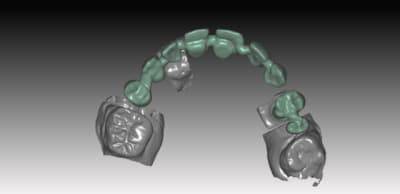

exemple de réalisation ..

sur ce cas pas de base titan, pas nécessaire because branemark , exagone externe base large ,bonne surface d'assise

Je posterais d autre cas sur du nobel activ (avec ambase ) strauman BL et NBreplace

faites l'économie d'un pilier , et appréciez le confort du transvissé :):)

donc voici comme promis piliers ZR sur base Titan

passivité total de l'armature , les piliers sont tous réglés , parallélisés lors de la modélisation de l'ensemble . l'usinage des piliers et de l'armature ce fait séparement pour encore qualité d'ajustage..

Dans le ce cas present Strauman BL 3.3 rc

collage des base titan avec du multilink automix

ce cas est en cour de réalisation , essayage de l'ensemble

déja validé ... je n ai pas de eu de photos , aucun blanchiment de gencive , merci l'ajustage des profils d'émergence dans le soft qui est vraiment bien fait ..